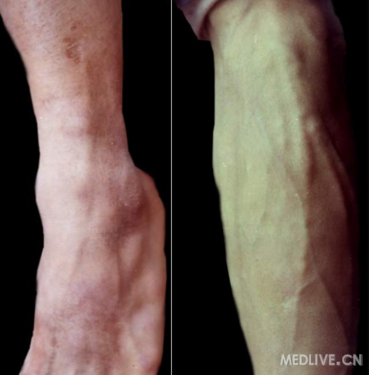

下肢麻风(结核样型)

足部麻风-腓浅神经粗大